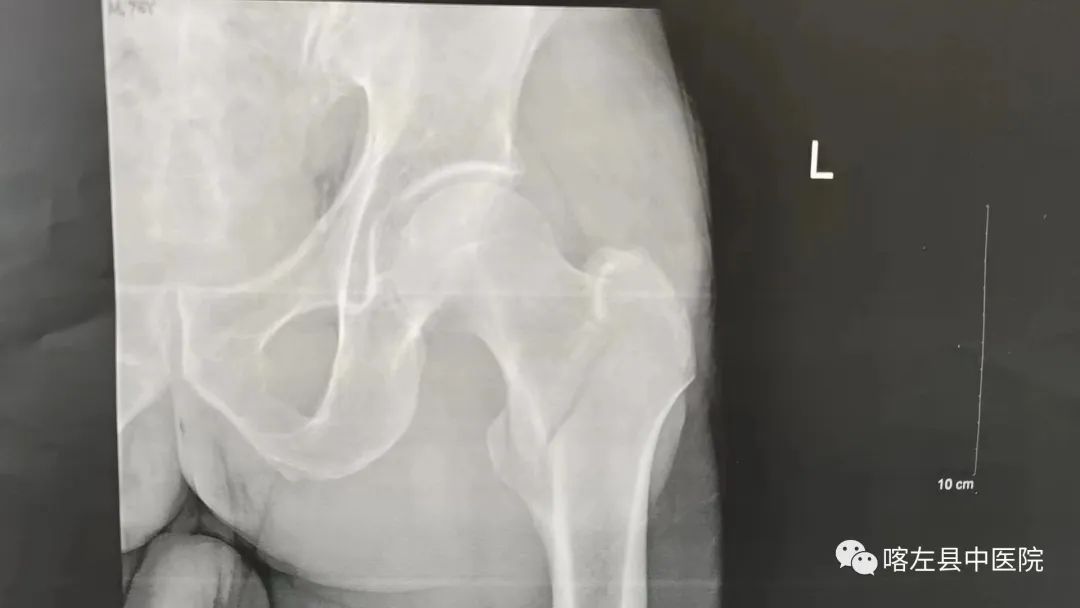

据了解,74岁的张大爷因曾患有急性脑梗死,尚在恢复期,走路时不稳不慎摔伤,导致左侧髋部疼痛不已,不能活动,家人们第一时间将其送至喀左县中医院就诊,经CT扫描检查,结果显示左股骨粗隆间骨折,被收住我院骨伤科。